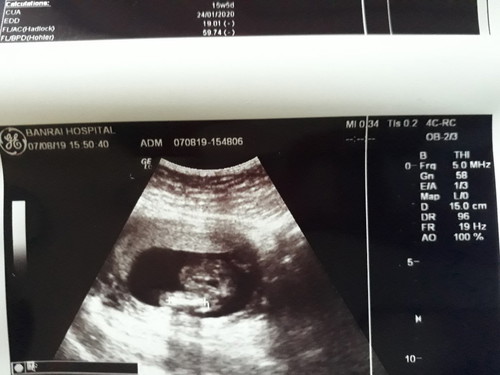

มีแม่ๆคนไหนพอจะดูออกมั้ยค่ะ!!

อยากรุ้ว่าเห็นเพศน้องรึป่าวค่ะ?

ดูยากอยู่นะคะ แต่ขอเดาว่าชายละกันค่ะ ^^